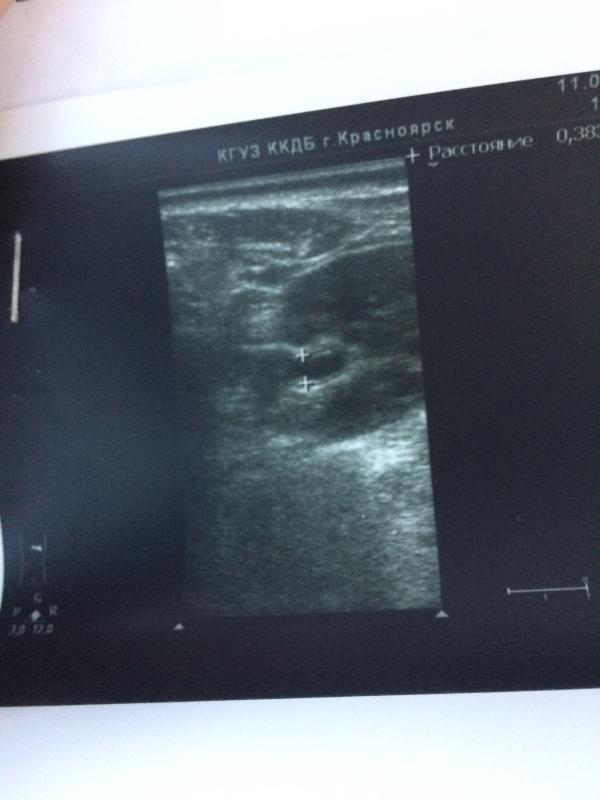

DS гидронефроз правой почки😱 страшно услышать маме такие слова, а плюс интернет-почти обморок...итак на узи в 2 месяца увидели уширение лоханок, направили к урологу, в 3 мес снова узи, размер увеличился😭 направляют на подтверждение в краевую детскую для установки степени 1,2...и вот спустя 3 часа посещений и ожиданий проходим снова узи... И УРА ВСЕ В НОРМЕ !!! Так что если услышите такое слово, не впадайте в панику, все может быть ХОРОШО! Всем добра✌🏻 PS тетя Надя, как говориться, должна умирать ...